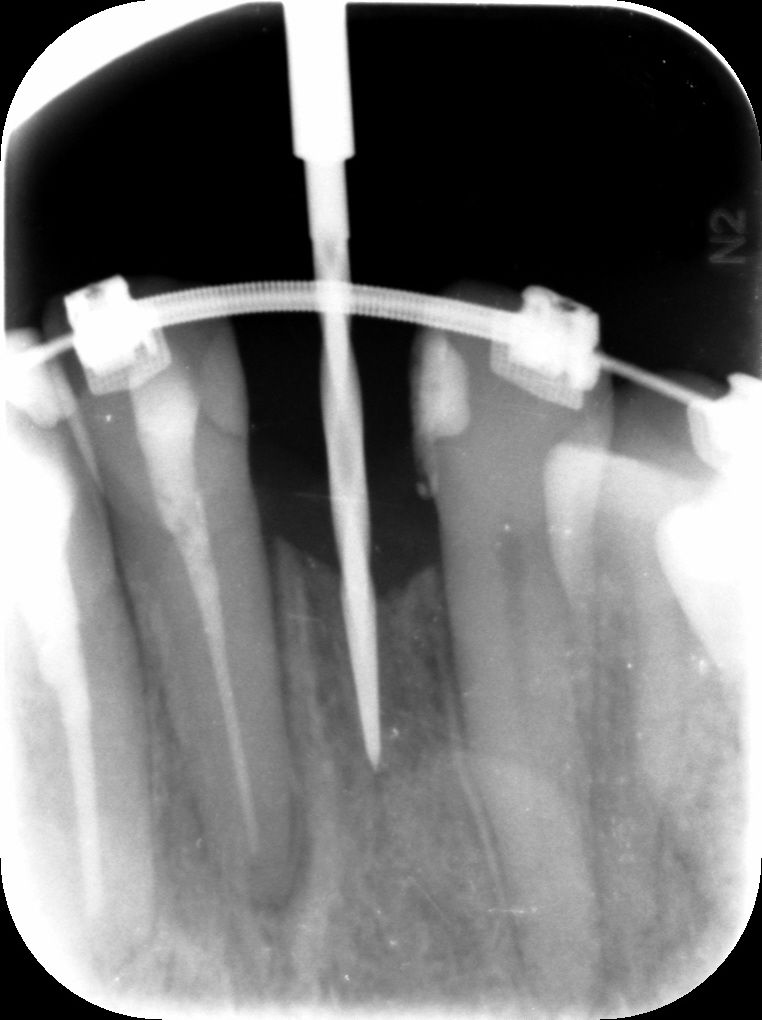

Surgical procedure

To reduce scar formation a marginal incision was made from #13 to #11, with a distal releasing incision at #13 (Figs. 4,5). The flap was deflected at the exposed bone – a narrow ridge in all dimensions (Figs. 6,7). After the pilot drilling and x-ray control of the axis (Figs. 7-9), the preparation of the implant bed was continued with the 2.2mm drill and the profile drill (Figs. 10-13). Next, the 2.9mm Straumann® BLT implant (Roxolid®, SLActive®) was inserted with a primary stability of 25Ncm, and the anatomical healing abutment was then connected (Figs. 14-18). Due to the limited bone thickness in the buccal region and a small coronal dehiscence, bone augmentation with botiss cerabone® and a Jason® membrane was also performed (Figs. 19-23). The flap was closed passively with 5-0 Prolene sutures (Figs. 24-27). The patient was prescribed antibiotics, analgesia and anti-inflammatory medication, as well as chlorhexidine rinse for 1 week. Suture removal and subsequent healing was uneventful.